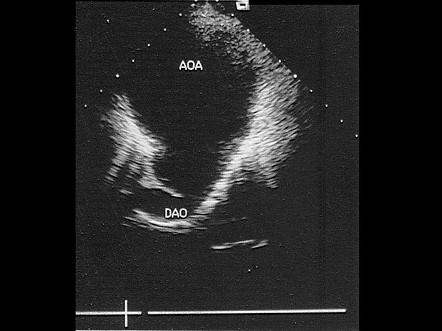

该病例最可能诊断?(?)A.真性动脉瘤B.假性动脉瘤C.夹层动脉瘤D.以上都不是E.主动脉瓣狭窄

选项 A.真性动脉瘤 B.假性动脉瘤 C.夹层动脉瘤 D.以上都不是 E.主动脉瓣狭窄

答案 A